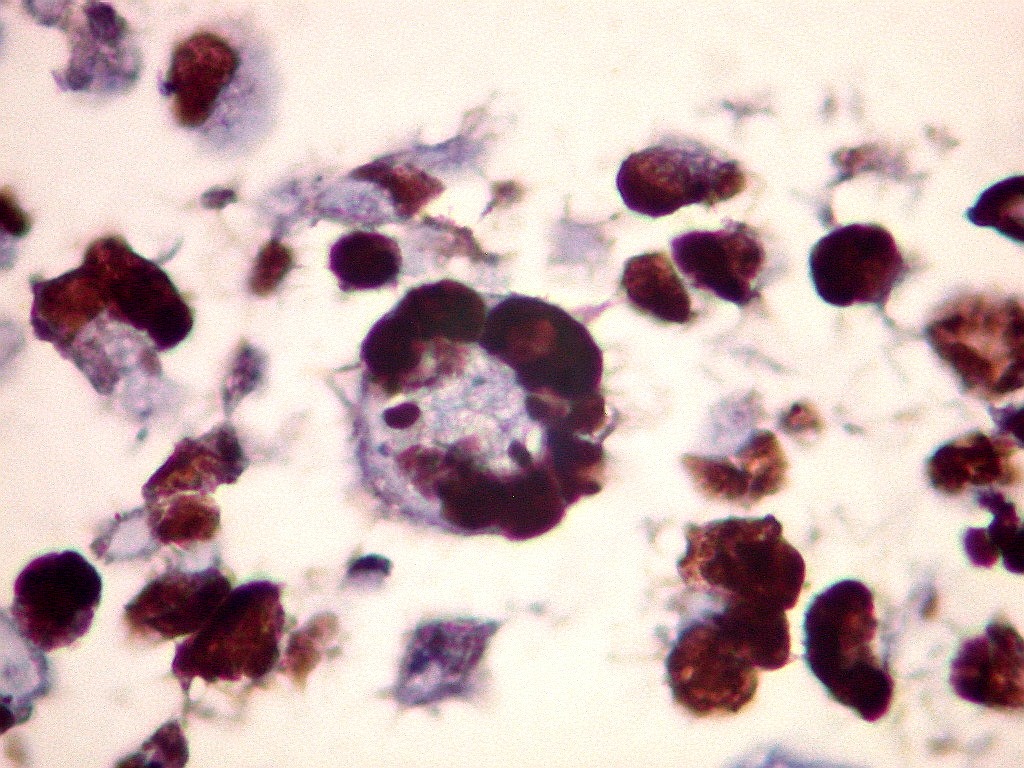

Ki67.      Positivo em cerca de 90% das células neoplásicas (altíssimo índice proliferativo).  Evidencia a morfologia arqueada dos núcleos, deformados pelos corpúsculos rabdóides.  Há poucas células neoplásicas não marcadas.